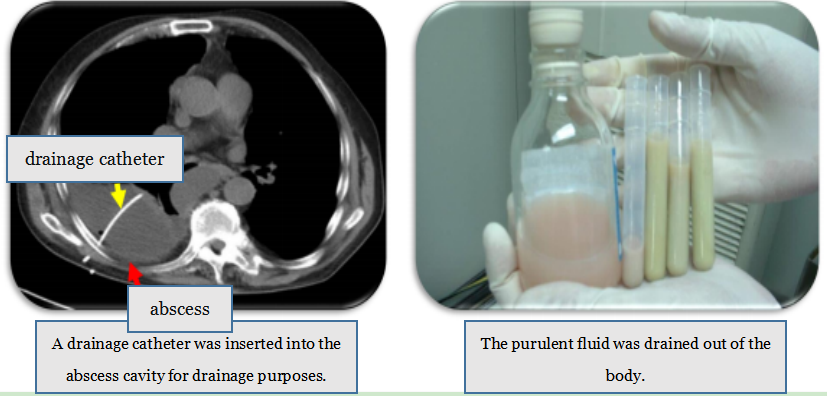

2. Abscess Drainage with Catheter Placement